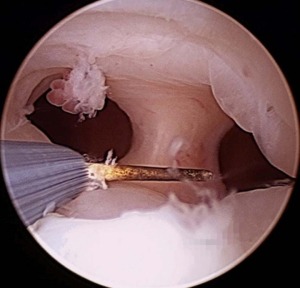

Polipectomia

Consiste na retirada de pólipos endometriais por meio de histeroscopia. Indicado para remover pólipos que podem causar sangramento uterino anormal.